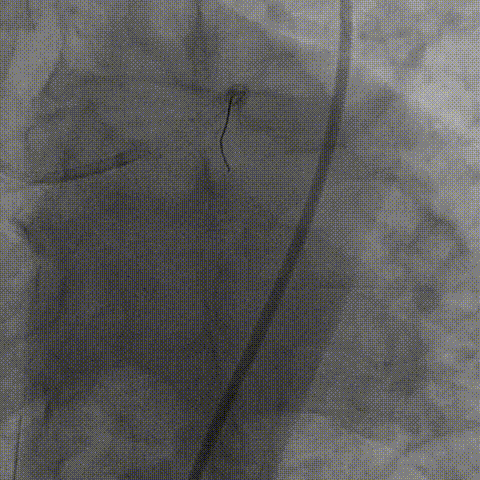

左冠造影

考虑到患者钙化严重且弥漫,为精准化钙化病变预处理方案,对患者进行IVUS检查,但超声导管无法通过病变部位;

启动主动旋磨,并选择1.75mm直径磨头以14-18万转/分对左主干钙化病变进行旋磨治疗;

在磨头通过靶病变后,终止旋磨,选取3.0NC球囊进行20ATM扩张,结果球囊膨胀并不理想;

为充分打开钙化,并获得更大管腔面积,故选用shockwave 3.5*12mm对球囊膨胀不理想处进行钙化断裂,经过8个周期治疗后,钙化环充分断裂。随后顺利植入支架,术后效果十分满意;

病变部位旋磨后,振波后超声对比